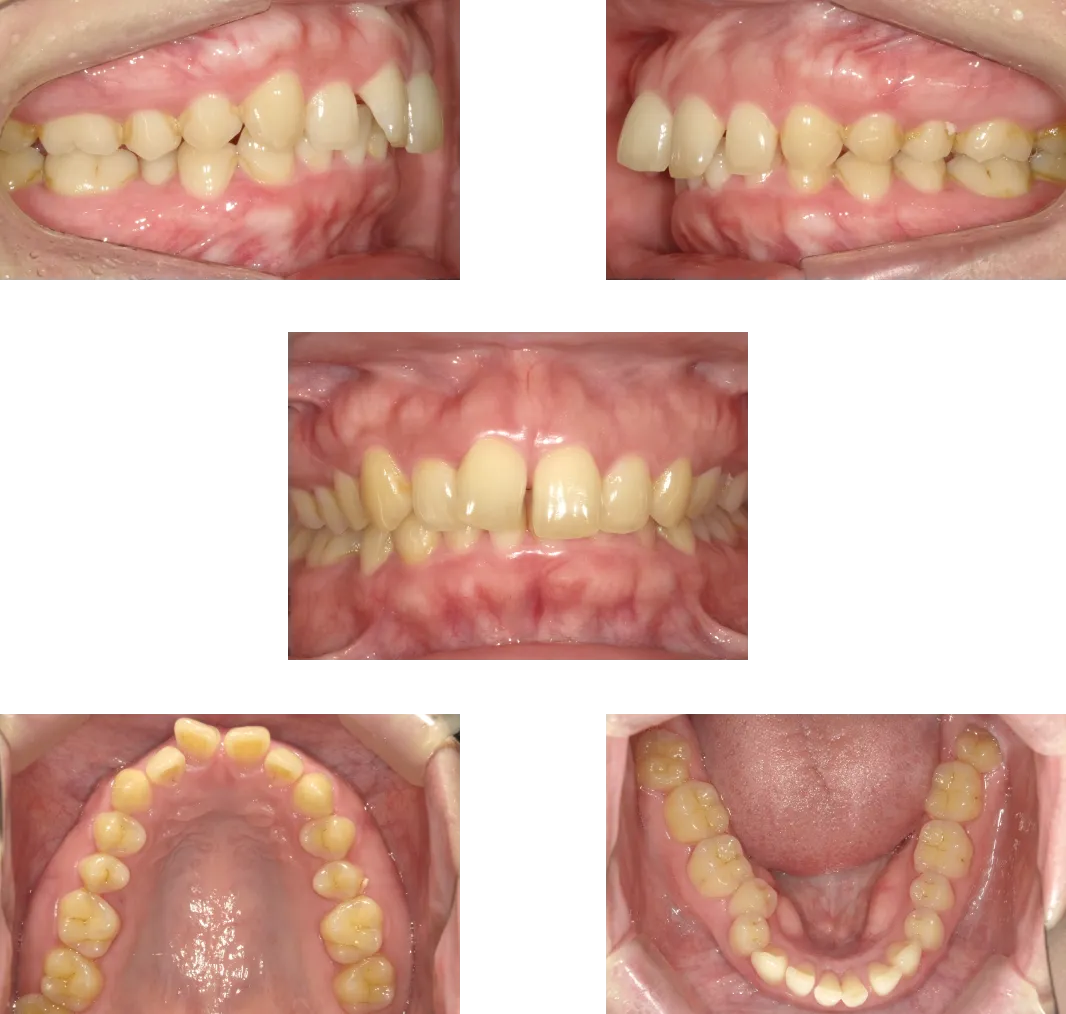

上顎前突 -15歳-

• Before

• After

診断

上顎の前歯唇側傾斜

治療期間

1年6ヶ月+保定期間2年

料金

950,000円

抜歯

なし

リスク

痛み、軽度の歯根吸収、術後の変化